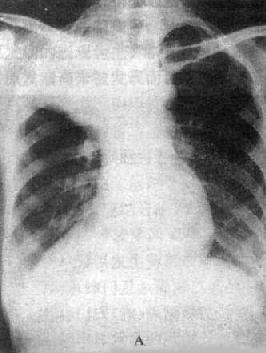

2)右肺中叶不张:较为常见,后前位表现为右肺下野内侧靠心右缘现上界清楚下界模糊的片状致密影,心右缘不能分辨(图3-1-9)。侧位上表现为自肺门向前下方倾斜的带状或尖端指向肺门的三角形致密影(图3-1-9)。上、下叶可有代偿性肺气肿。

图3-1-9 右肺中叶肺不张(正、侧位)

图3-1-11 肺实变(右中叶大叶性肺炎)

相当于右肺中叶密度均匀增高,后前位上,上缘清楚,下缘模糊,

侧位上呈三角形致密影,尖端在肺门区